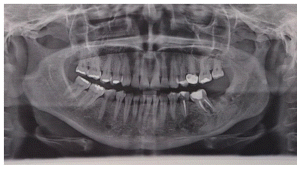

On 2006 A 47-year-old woman presented to the consultation and reported discomfort in the left mandibular area, in the panoramic x-ray a well-defined radiolucent area can be observed, apparently well encapsulated, which extends from the first premolar to the second molar with mobility grade one of the molars. An incisional biopsy was performed. The findings were semi-liquid content of yellowish, brown with pus content (Figure1).

Enucleation of the lesion and curettage of the area were performed, as well as a endodontic treatment of the second premolar, first and second lower left molar. The patient remained stable for 6 years when a panoramic rx was taken on 03/13/2012 as a control (Figure 2).

Subsequently, seven months later, on 10/17/12, she presented endodontic problems in the previously treated teeth and lost the second lower left molar after the revision, radiographic changes were seen in the panboramic X ray. (Figure 3) An incisional biopshy was taken,10 months 15/08/2013 based on the diagnosis of the biopsy, a CT scan was taken and a stereolithography model was developed for the surgery of the central ossifying fibroid by mandibular resection.